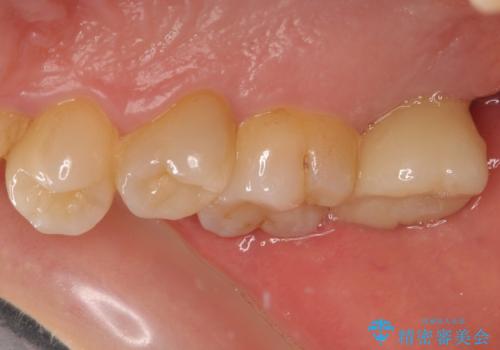

抜歯後に不快感は消失したのですが、手前の歯にあるむし歯が痛み出してきたため、セラミックインレーにて修復治療を並行して行いました。